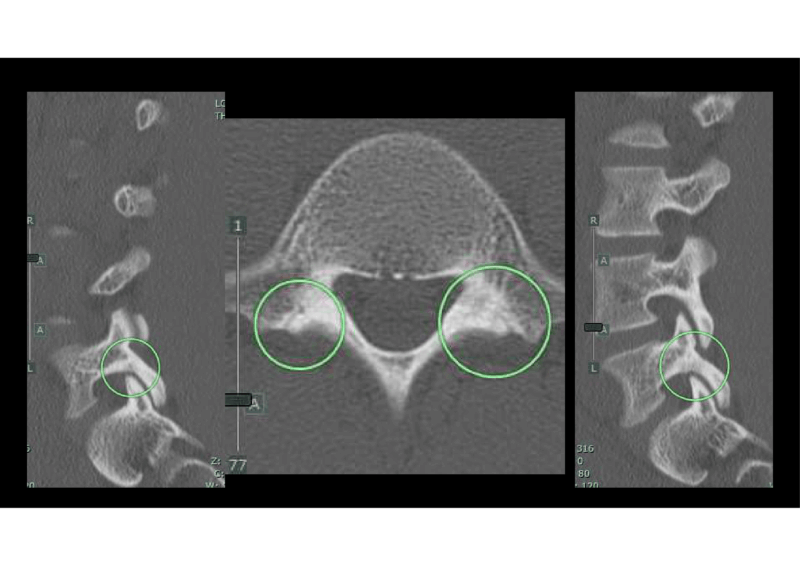

CT、MRIを即時に撮影し、受診から1時間以内で完了

CTでわずかな骨折線、MRIでは両側L5椎弓根に脂肪抑制画像で高信号を認めた。

診断は初期腰椎分離 西良教授の結果では3か月安静、硬性コルセットで>90%骨癒合